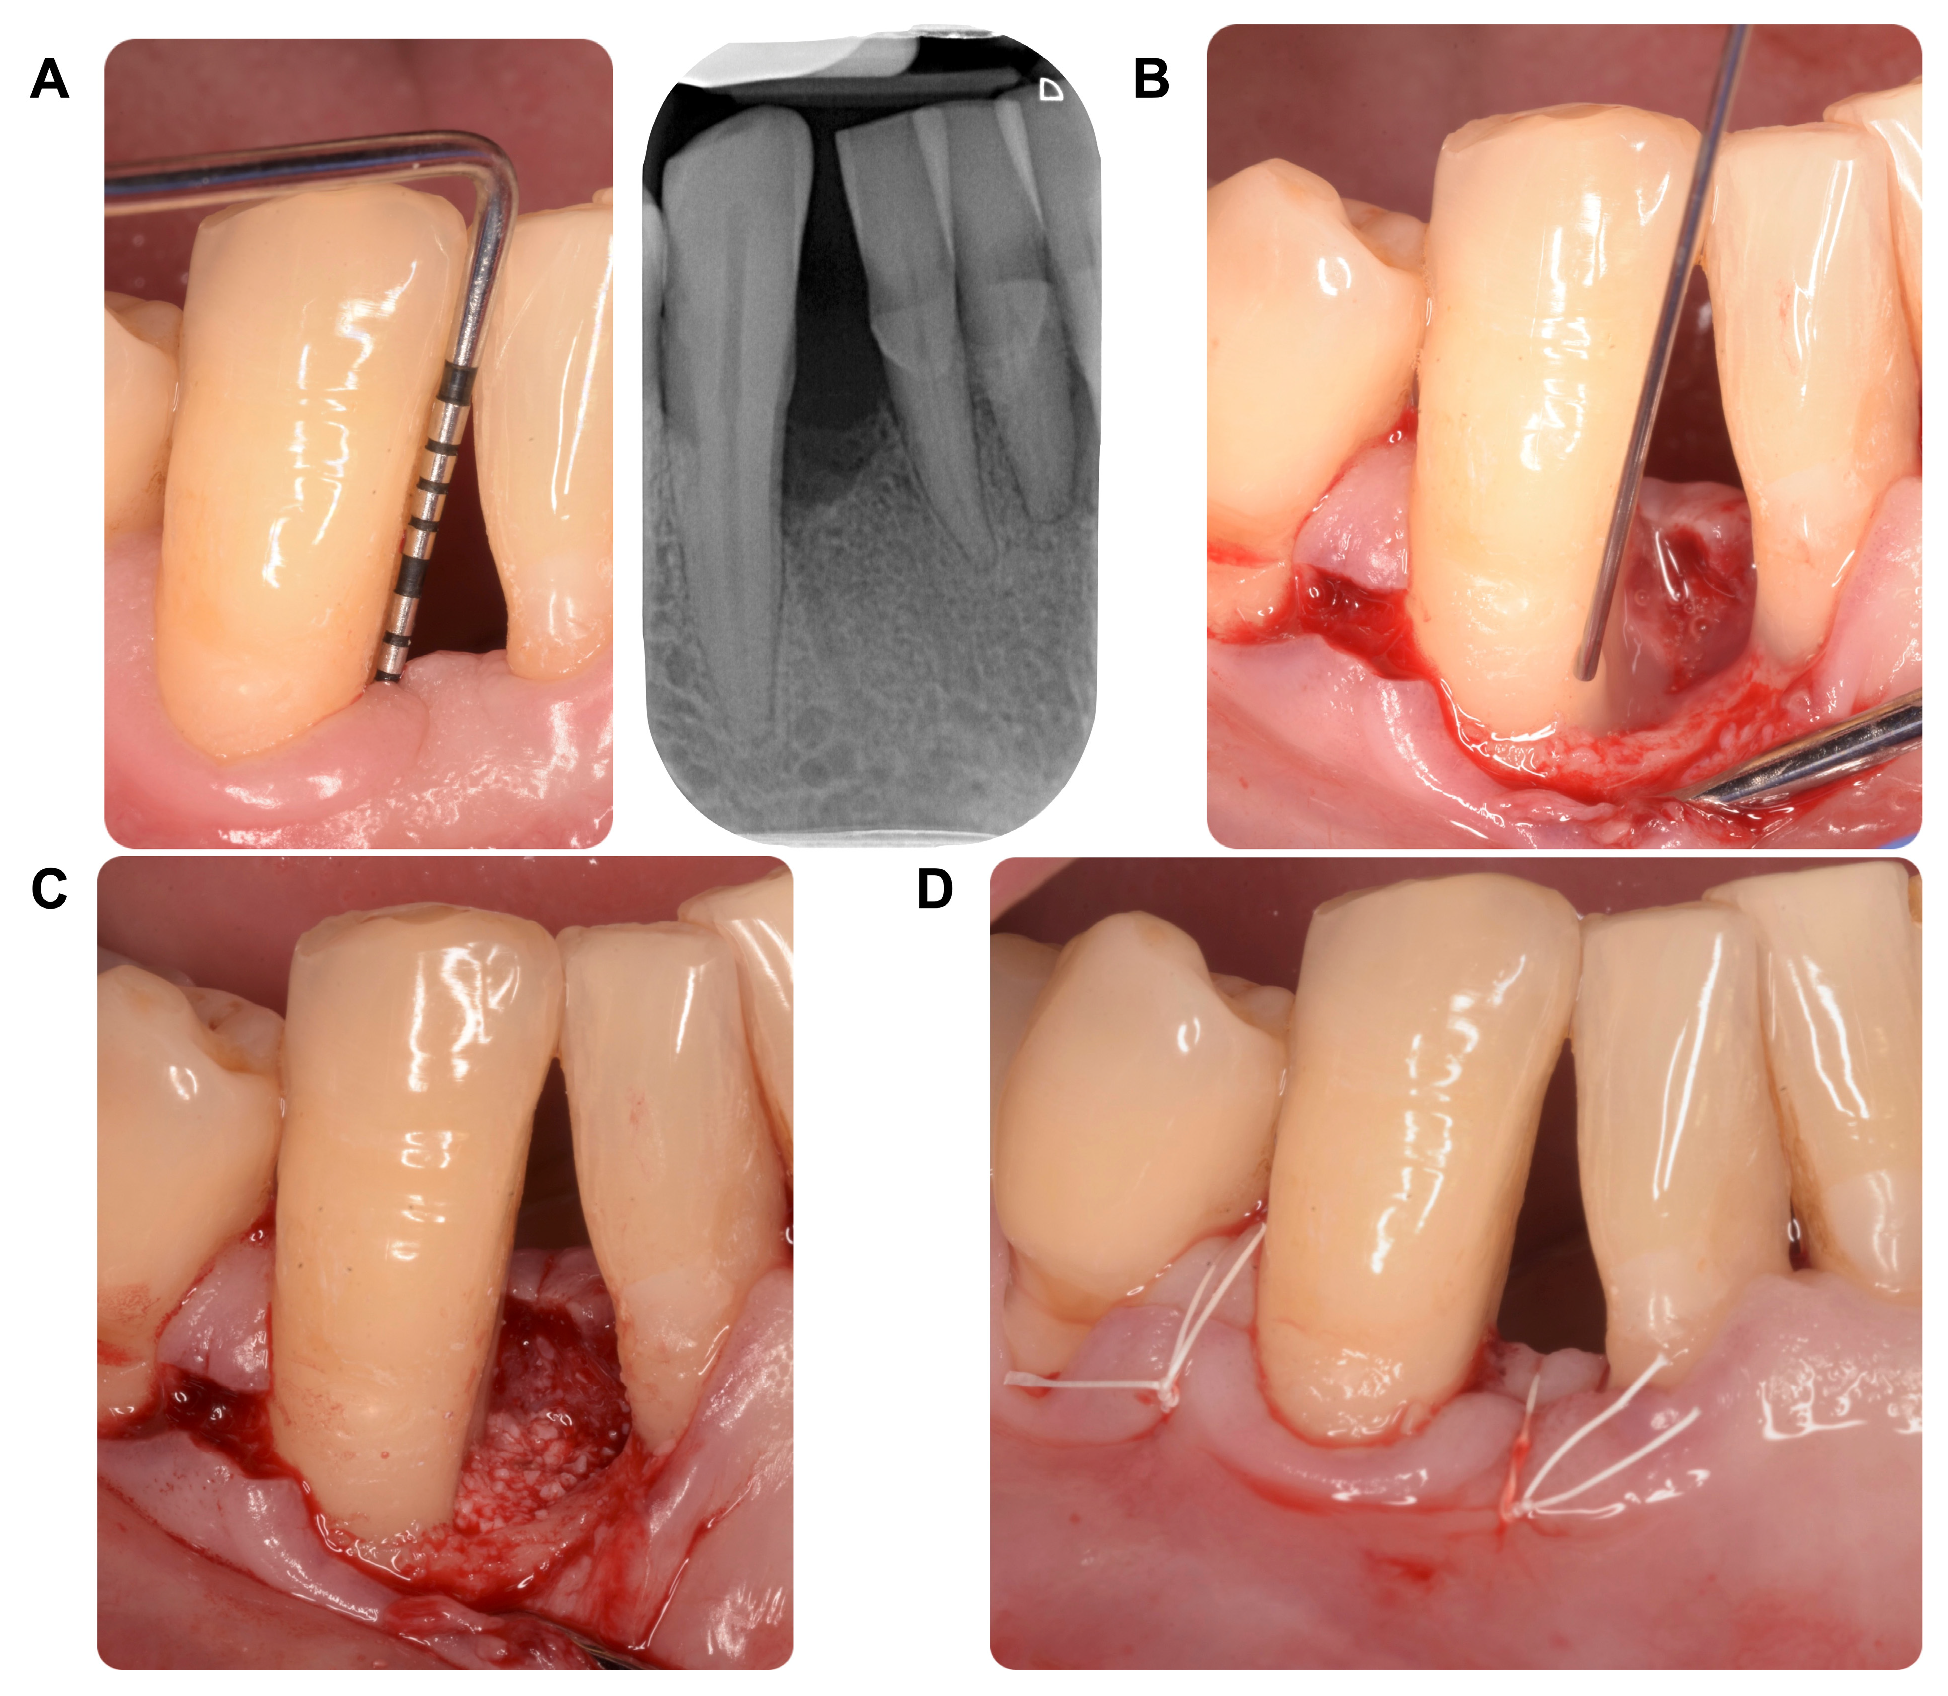

4.2. Intervention